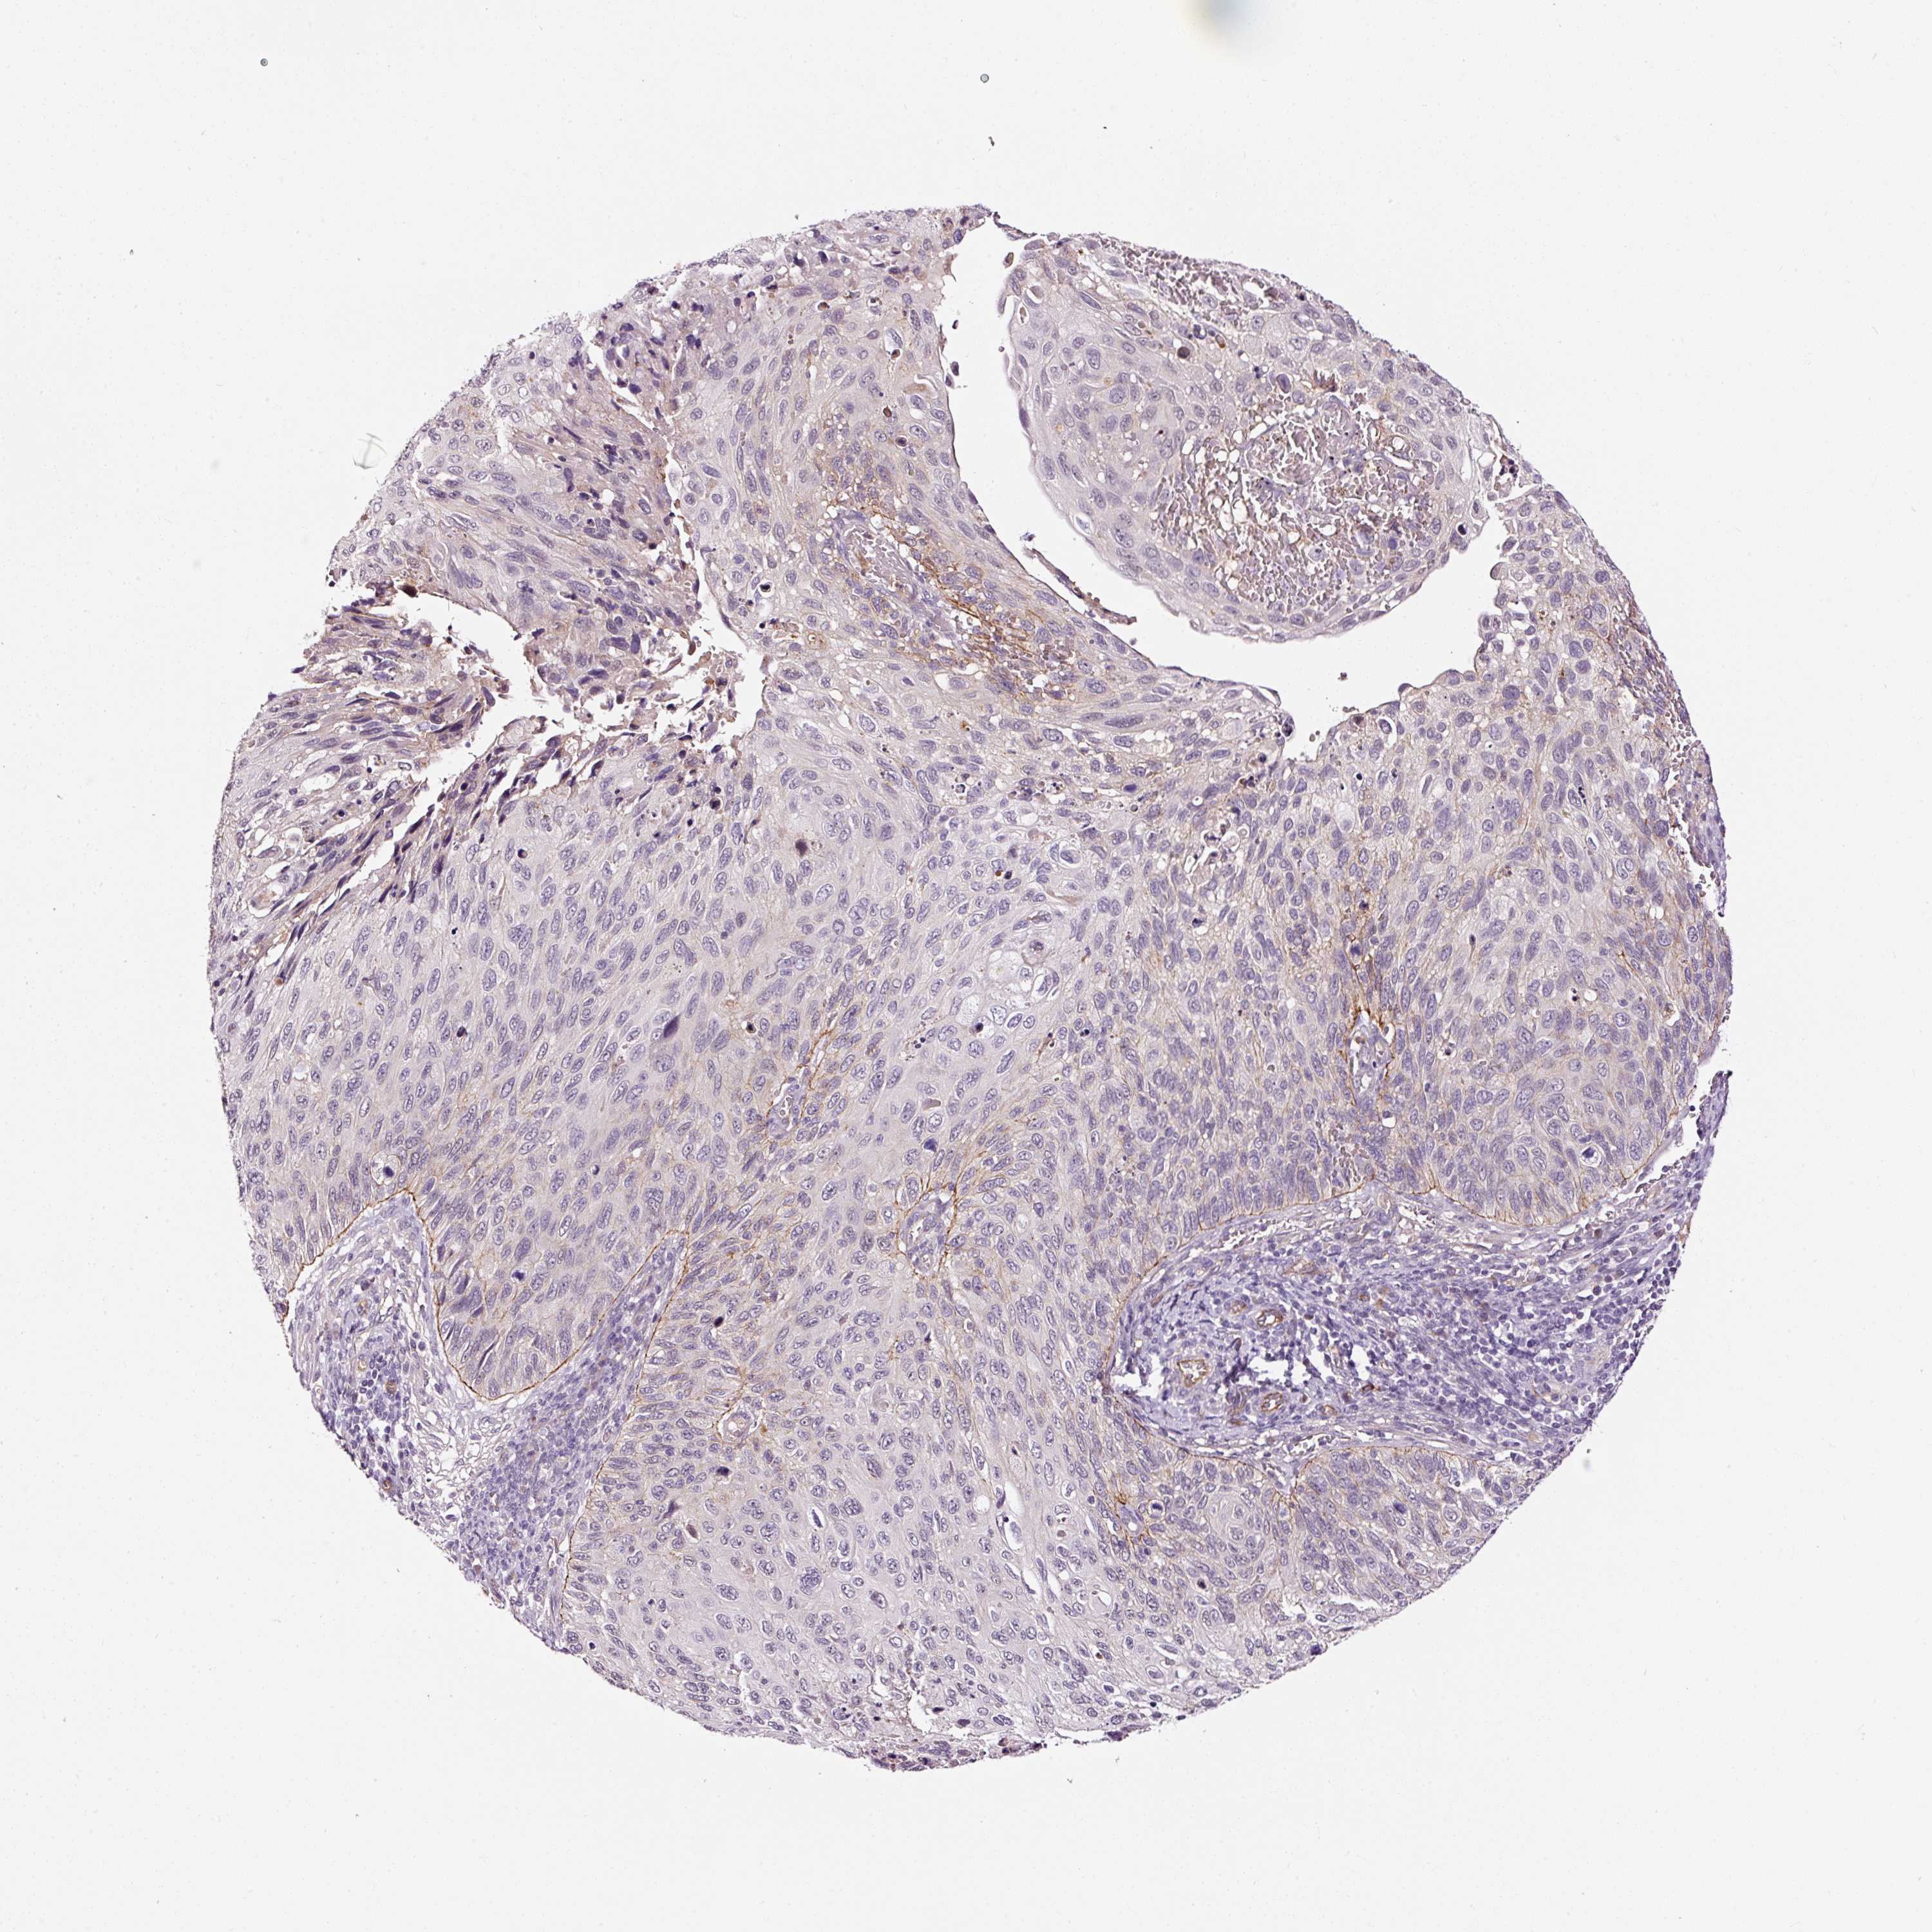

CERVICAL CANCER - Protein expressioni

A mouse-over function shows sample information and annotation data. Click on an image to view it in a full screen mode. Samples can be filtered based on level of antibody staining by selecting one or several of the following categories: high, medium, low and not detected. The assay and annotation is described here.

Note that samples used for immunohistochemistry by the Human Protein Atlas do not correspond to samples in the TCGA dataset.

Antibody stainingi

Antibody staining in the annotated cell types in the current human tissue is reported as not detected, low, medium, or high, based on conventional immunohistochemistry profiling in selected tissues. This score is based on the combination of the staining intensity and fraction of stained cells.

Each image is clickable and will lead to virtual microscopy that enables deeper exploration of all samples and also displays staining intensity scores, fraction scores and subcellular localization as well as patient and tissue information for each sample.

Antibody HPA049395

Antibody HPA053288

Staining

High

Medium

Low

Not detected

Intensity

Strong

Moderate

Weak

Negative

Quantity

>75%

75%-25%

<25%

None

Location

Nuclear

Cytoplasmic/membranous

Cytoplasmic/membranous,nuclear

Squamous cell carcinoma, NOS

Adenocarcinoma, NOS